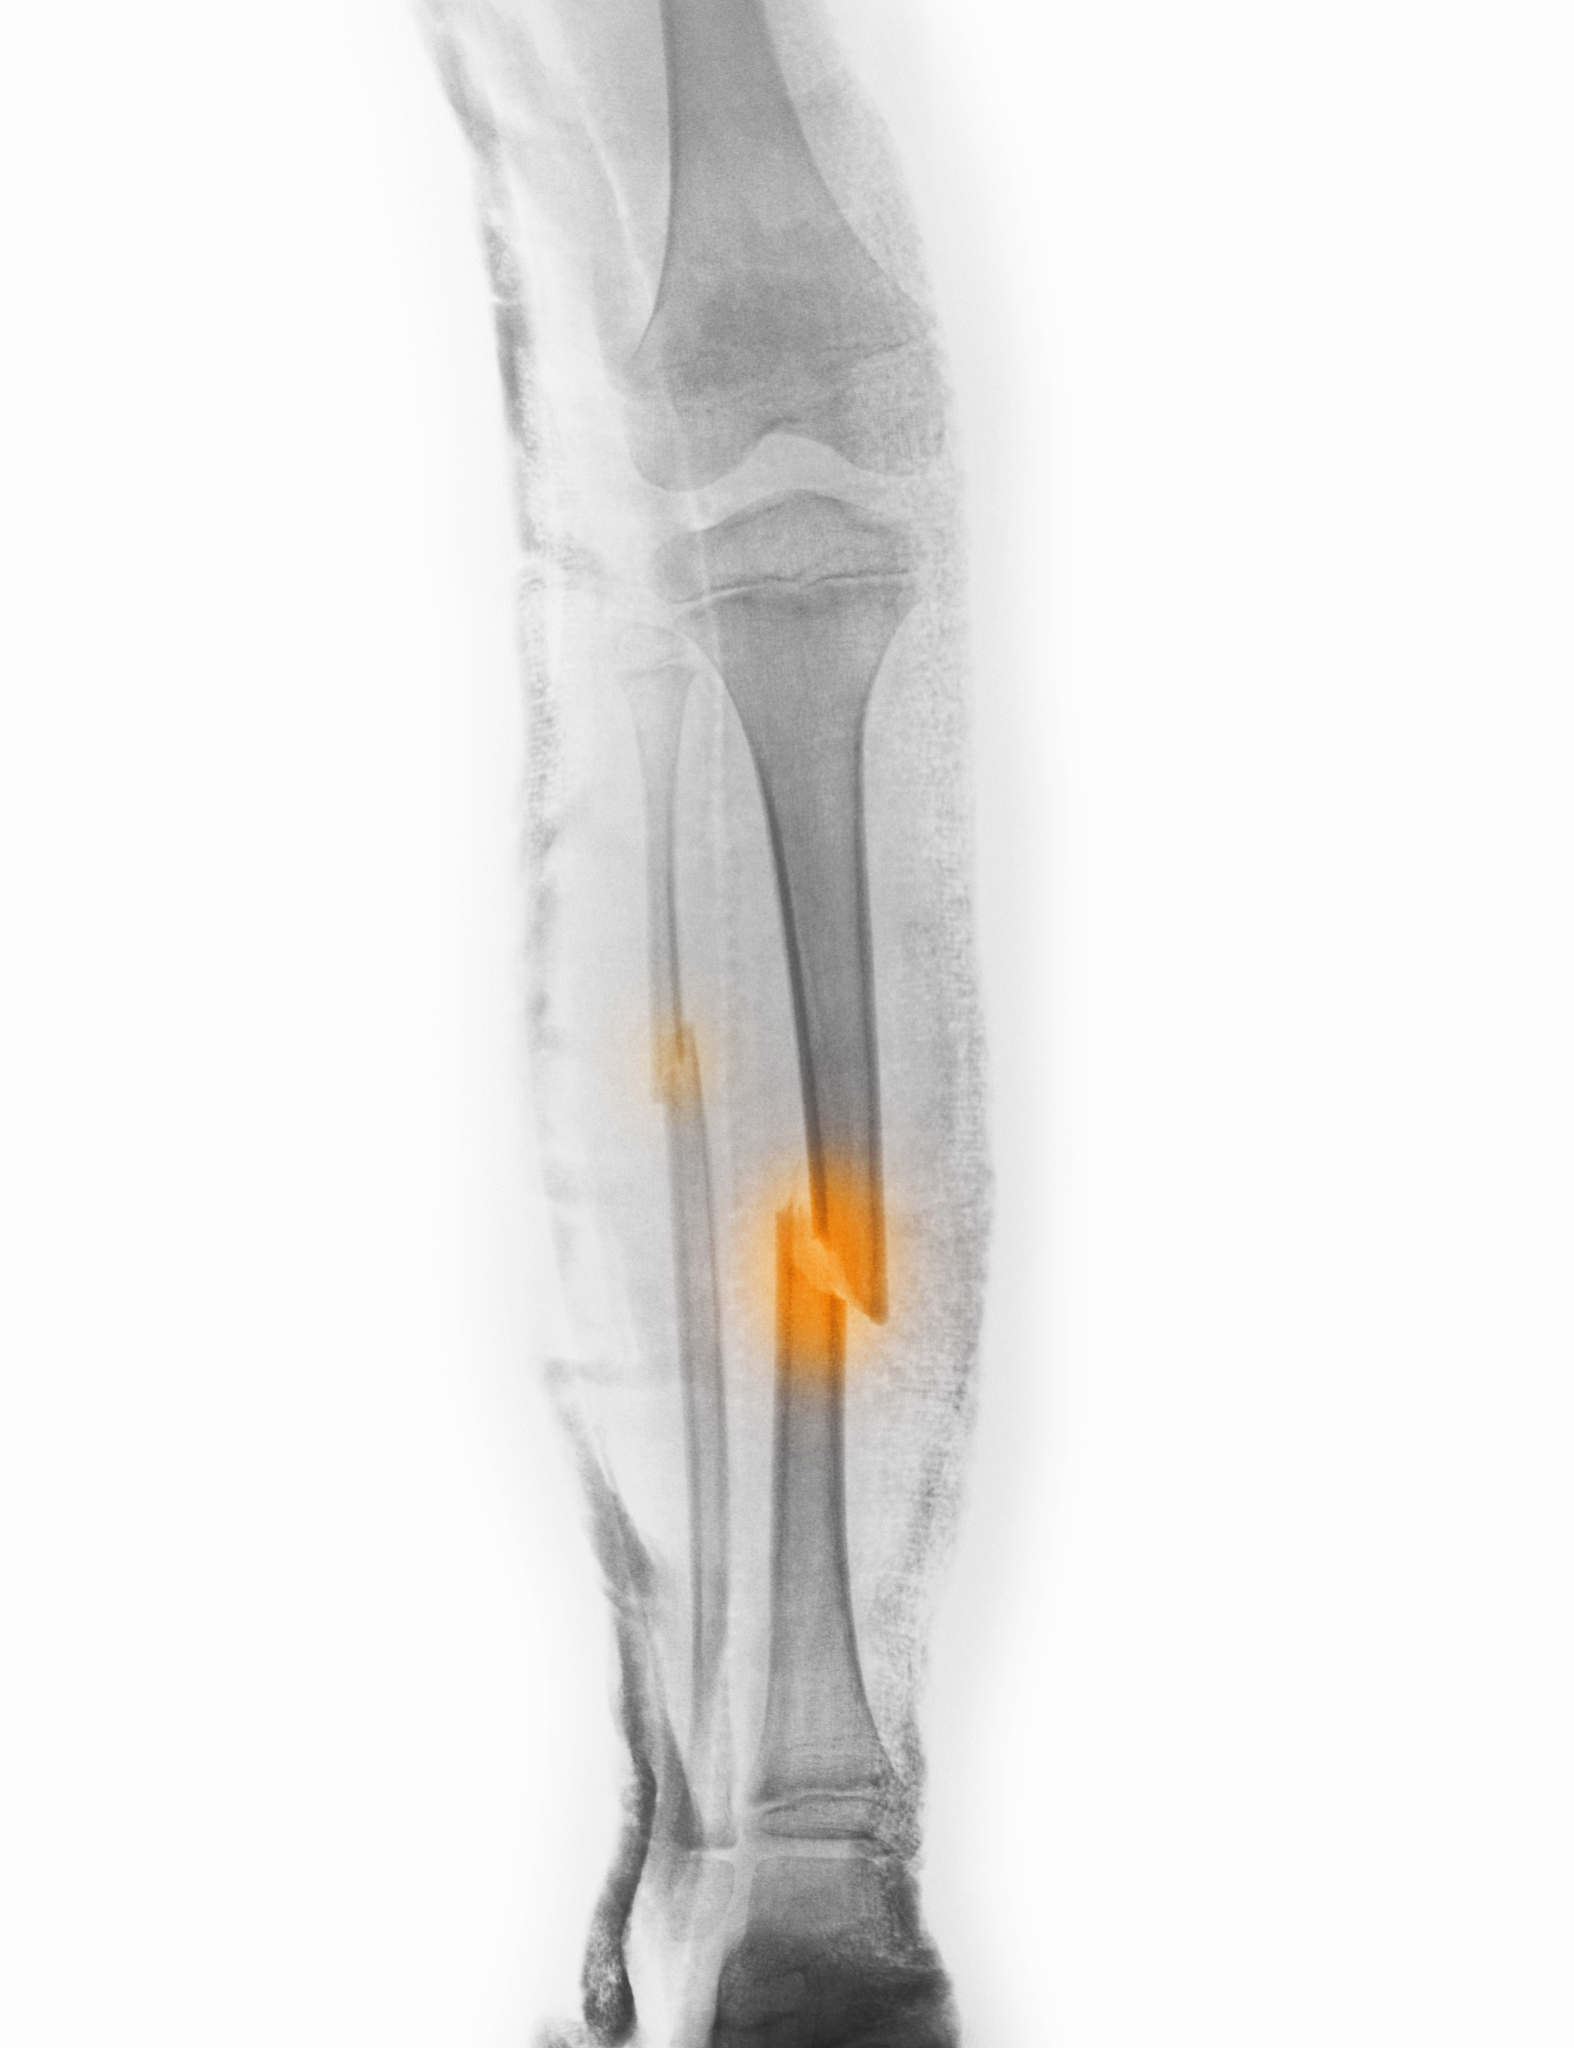

小腿骨折症状1 疼痛:小腿骨折时会感到剧烈的疼痛尤其是在受伤部位。2 肿胀:小腿骨折后周围的软组织可能会肿胀导致肿胀和疼痛。3 瘀伤:小腿骨折时周围的皮肤可能会出现瘀伤或淤血的迹象。4 受伤部位变形:小腿骨折时受伤部位可能会出现明显的变形如突起或凹陷。5 无法支撑体重:玉蒲团小腿骨折后患者可能会感到无法支撑体重不能正常行走。6 活动范围受限:小腿骨折后患者可能会感到运动和活动的范围受到限制因为骨折